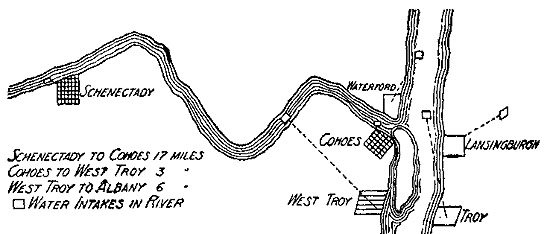

80 Typhoid Epidemic in the Mohawk-Hudson Valley